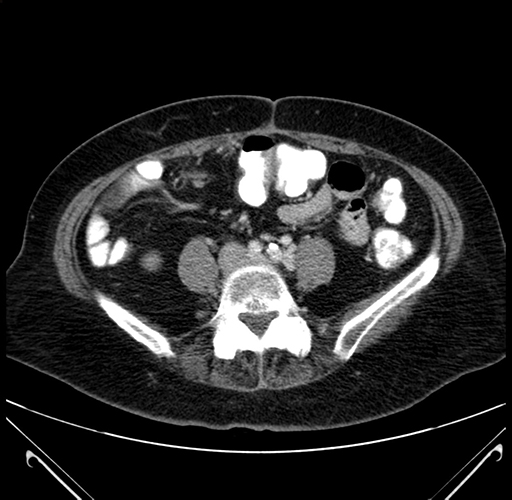

Pre-Chemo: Coronal Venous

Coronal Venous